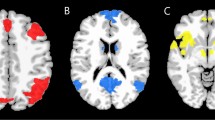

Recent evidence suggests that the brain intrinsic activity during rest might be as significant as task evoked activities and consumes considerable energy linked to neural signaling processes. We performed an fMRI study recently aiming to compare the differences in brain activity between patients with obsessive-compulsive disorder and healthy volunteers during a simple suppression paradigm. We hypothesized that the patients with obsessive-compulsive disorder would show default mode network (DMN) connectivity dissociations from healthy individuals. OcD patients had higher connectivity (p < 0.05) than controls between right inferior parietal lobe (IPL) and left ventral medial prefrontal cortex (MPFC).